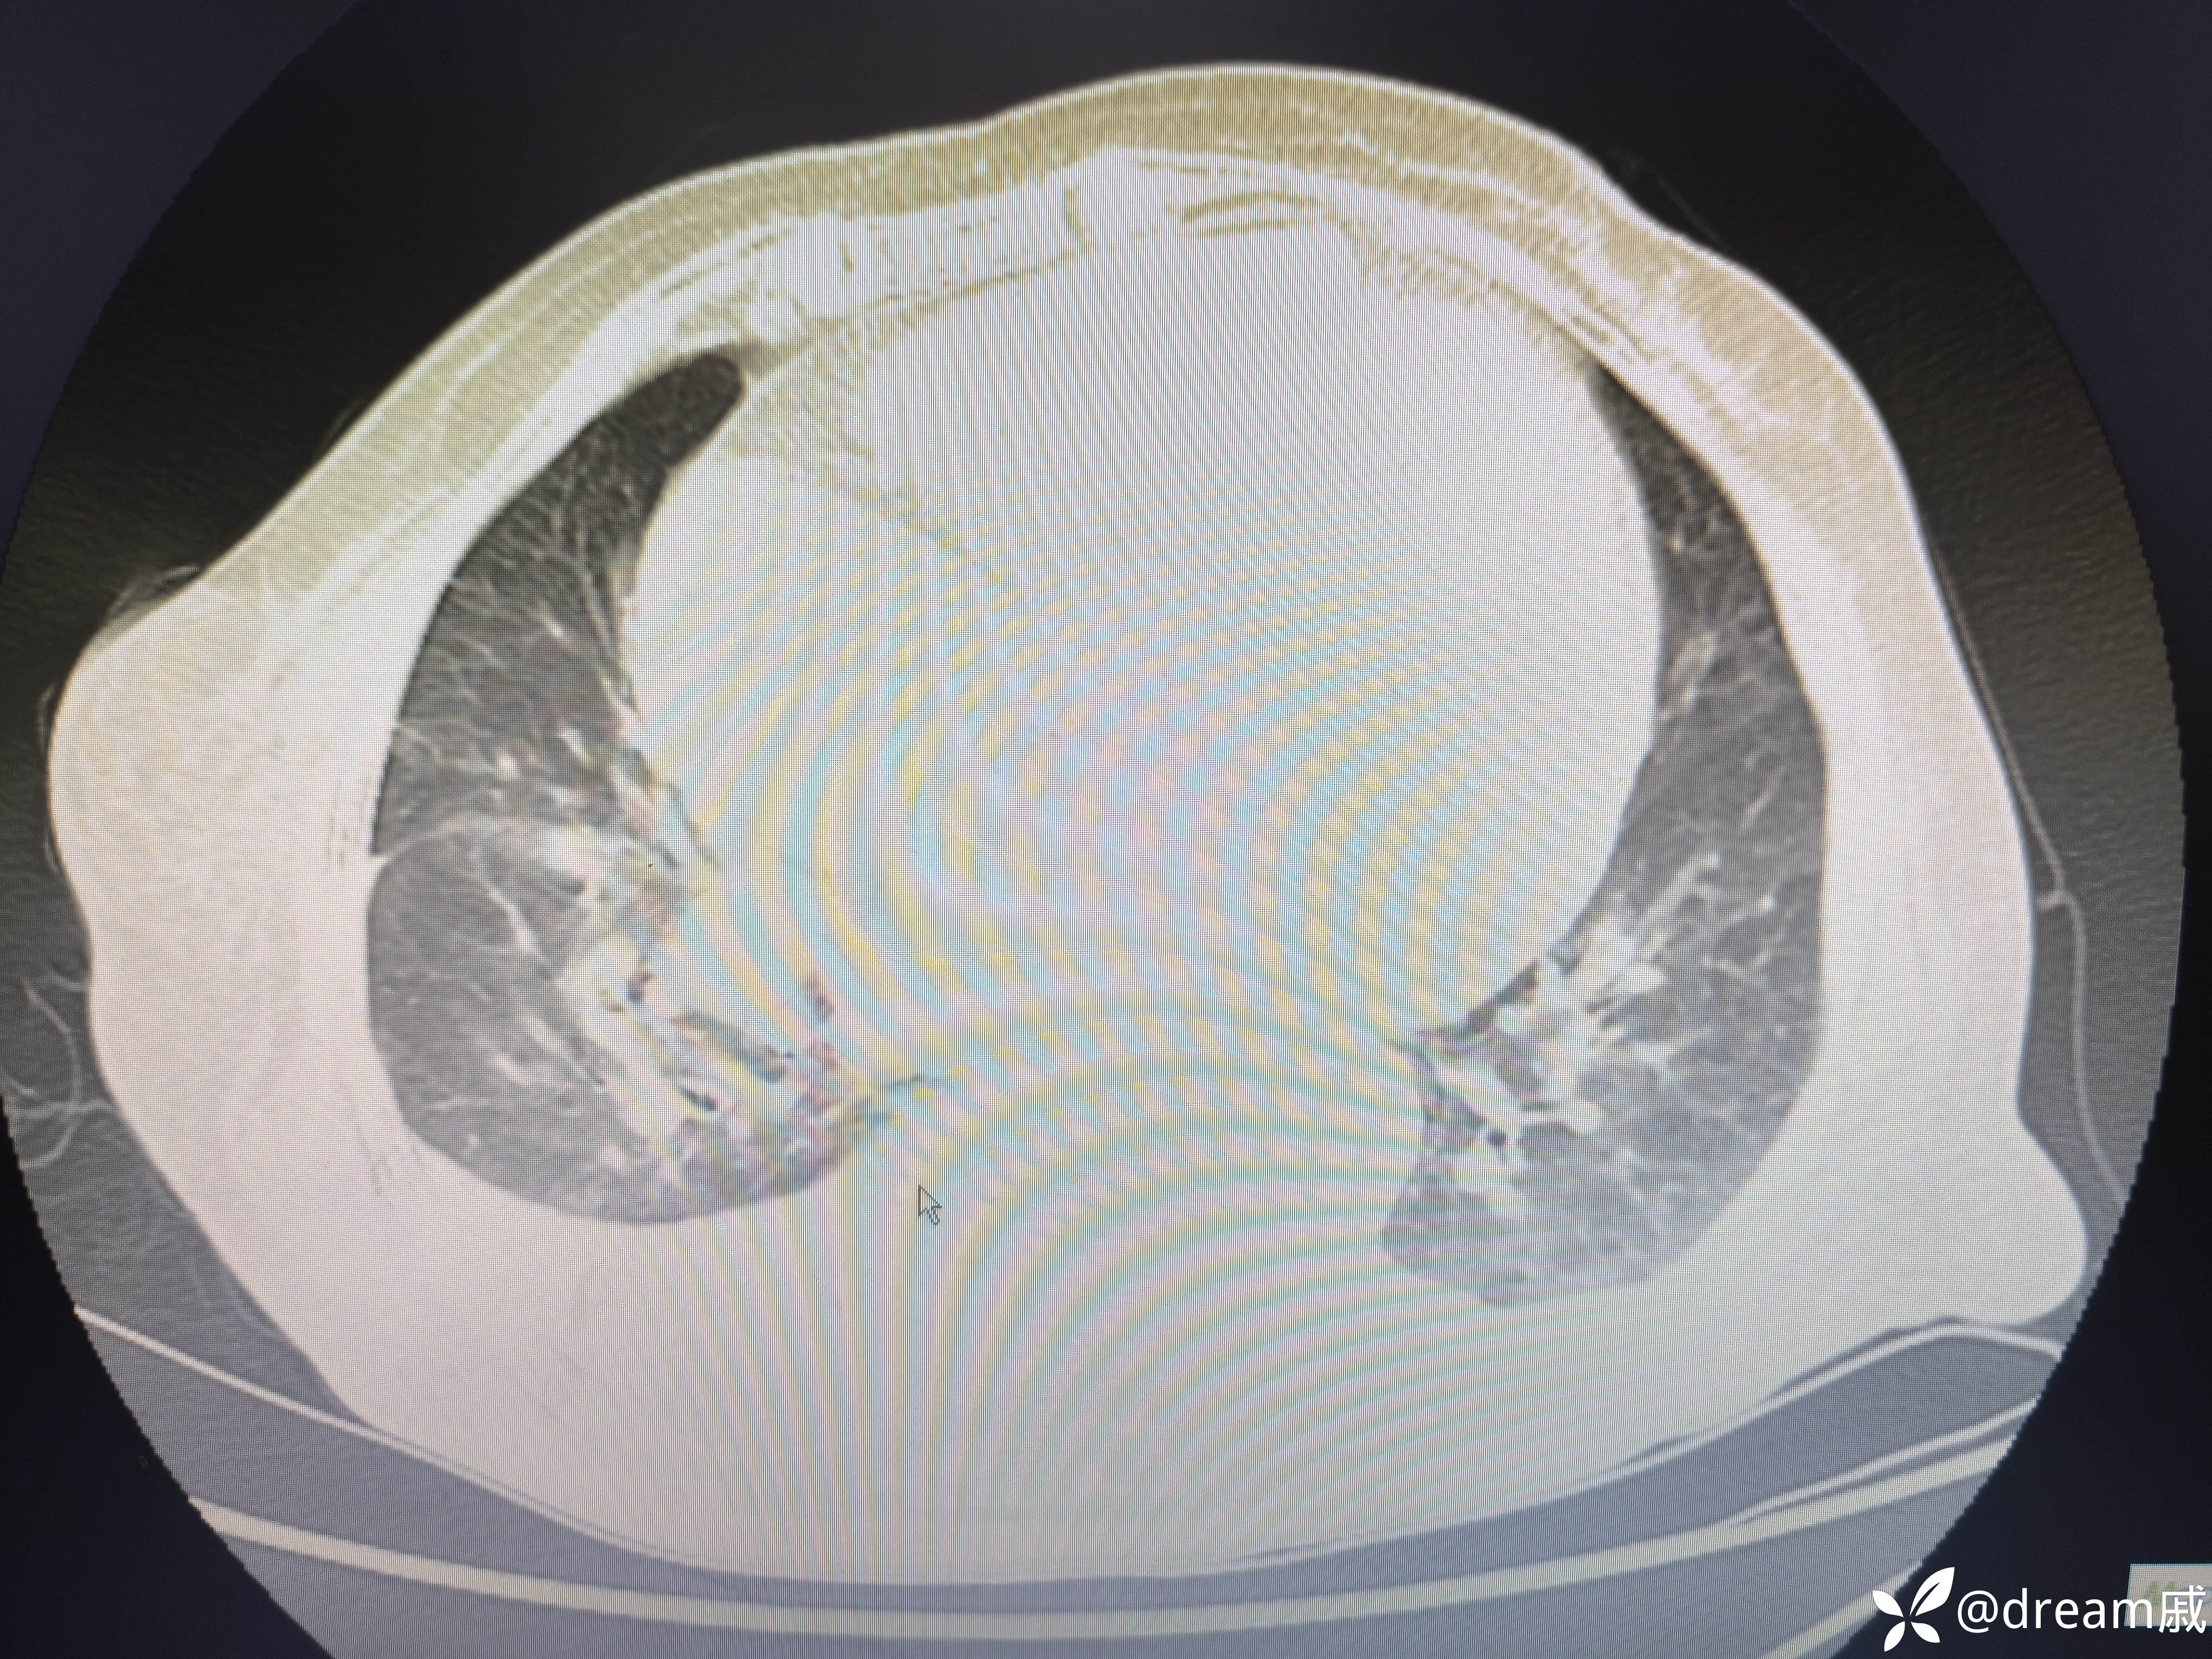

5月27日复查CT如下